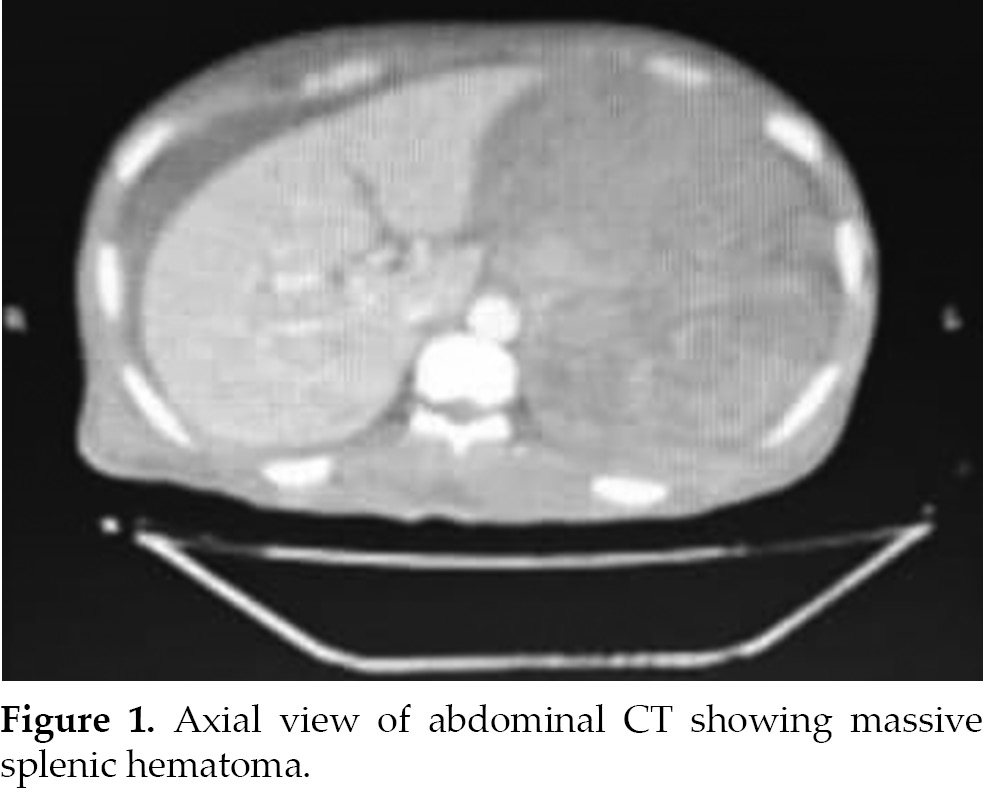

Splenic rupture, although rare in dialysis patients, can be life-threatening. In this case, a 45-year-old man with kidney failure on hemodialysis experienced sudden and severe abdominal pain in the left flank, without any history of trauma. He displayed

symptoms of hypovolemic shock, characterized by pallor, hypotension, and tachycardia. Additionally, he had abdominal distension and tenderness. An abdominal CT scan revealed a splenic hematoma and intra-abdominal hemorrhage. The patient required a

splenectomy to address the ongoing bleeding, but unfortunately, he succumbed to post-splenectomy sepsis 2 weeks later.